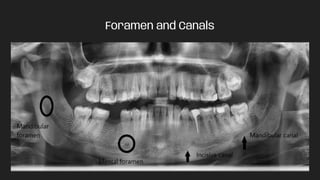

Foramen and Canals

Labelled Structures : 1)Mandibular Condyle 2) Coronoid Notch 3) Coronoid process 4) Ramus of Mandible 5) Mandibular/Incisive canal